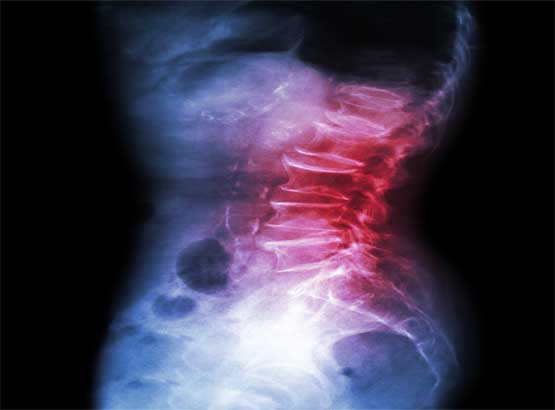

Brief profile: Dr Arghya Mukherjee, a university certified doctor for pain management with background knowledge of Anaesthesiology has been providing treatments for those affected with acute and chronic pain. Dr Arghya Mukherjee applies his expertise in a wide variety of advanced, minimally invasive procedures as part of a comprehensive approach to treat patients with acute and chronic pain.

Fields of expertise: Dr Arghya Mukherjee has special interest in Ultrasound guided acute and chronic interventional pain management procedures. He performs Fluoroscopy guided interventional pain management procedures for chronic and cancer pain as well with expertise.